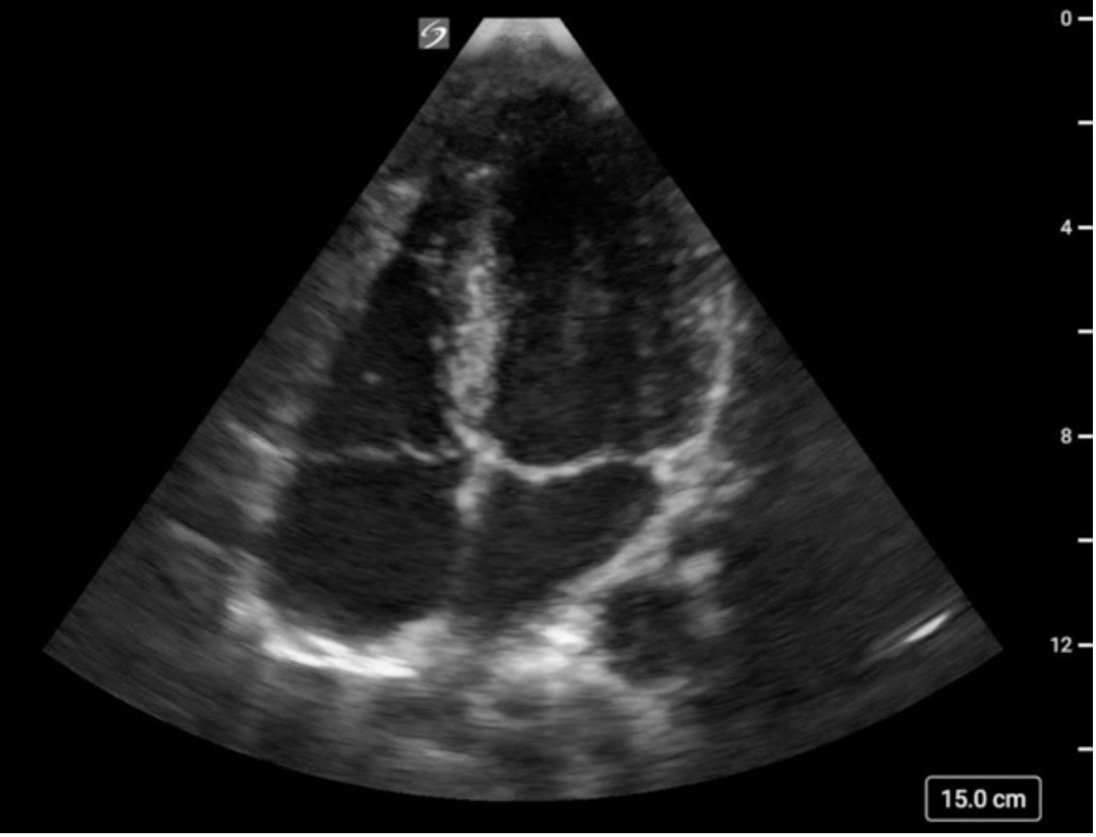

Subcostal Four Chamber

What am I Looking at?

The subxiphoid 4 Chamber view can be used to assess ventricular function, particularly during emergent situations, when access to the other windows is limited.

The left ventricle is seen in the far field with the septal and lateral walls in view. The RV is seen more anteriorly.

Figure 25. Subxiphoid 4 chamber with the LV walls labeled

What is Normal

Contractility:

All visible LV walls should demonstrate symmetric inward motion and thickening, moving toward the center of the ventricle in a coordinated fashion.

Figure 26. Subxiphoid 4 chamber view with normal LV function

What is NOT Normal

Decreased global function:

The LV walls will fail to contract effectively toward the center of the cavity during systole. Wall motion appears sluggish or diminished, and the overall inward movement and thickening are reduced (figure 27).

Figure 27: Subxiphoid 4 Chamber demonstrating reduced LV systolic function. Video courtesy of Dave Kirschner